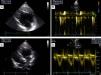

Apresentava em consulta uma pressão arterial de 96‐65mmHg e um sopro sistólico, grau II‐III/VI audível no 4.° espaço intercostal junto ao bordo esquerdo do esterno. O eletrocardiograma (ECG) de 12 derivações mostrava ritmo sinusal, 60bpm e pacing ventricular com sincronia AV mantida. A duração do QRS era de 196ms (Figura 1A). O ecocardiograma transtorácico (ETT) revelava um ventrículo sistémico (VD morfológico) dilatado (63mm) (Figura 2A), com função sistólica global deprimida (≤35% por método de Teicholz [não aplicabilidade do método de Simpson devido à morfologia do VD], relação dP/dt de 379mmHg/s), regurgitação aórtica moderada, regurgitação da válvula AV sistémica (morfologicamente tricúspide) moderada e uma pressão na AP estimada em 40mmHg. Não apresentava dessincronia AV (tempo de enchimento diastólico >40%, com uma boa separação das ondas E e A, sem truncagem da onda A); para a análise da dessincronia interventricular, apenas foi possível a quantificação do período de pré‐ejeção sistémico significativamente prolongado – 161ms (Figura 2B).

Ecocardiograma transtorácico realizado em paciente com transposição congenitamente corrigida das grandes artérias, antes (A, B) e após (C,D) a implantação do sistema de ressincronização cardíaca. Observa‐se uma redução da dimensão diastólica do ventrículo sistémico, de 63mm (A) para 58mm (C) – marcador de possível remodelagem reversa, bem como o desaparecimento do atraso eletromecânico sistémico quantificado pelo período de pré‐ejeção de 161ms (B) para 83ms (D).

Em consulta de seguimento aos seis meses verificou‐se melhoria da classe funcional de IC (classe I‐II da NYHA), redução da dimensão diastólica do ventrículo sistémico (de 63mm para 58mm) (Figura 2C), desaparecimento do atraso eletromecânico sistémico quantificado pelo período de pré‐ejeção (de 163ms para menos de 100ms) (Figura 2D), bem como uma melhoria da fração de ejeção (de ≤35% para cerca de 47% pelo método de Teicholz e melhoria da relação dP/dt de 379mmHg/s para 511mmHg/s).